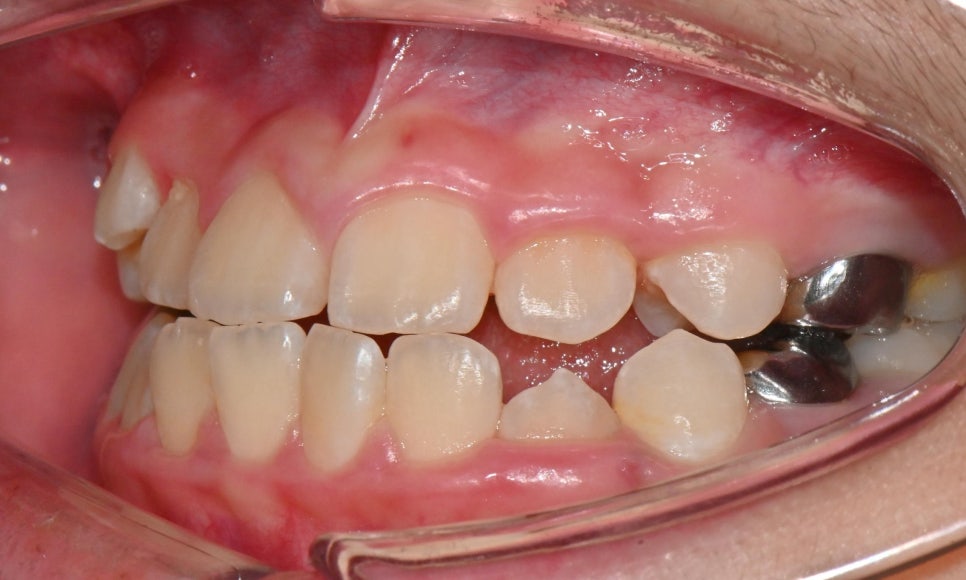

본 환자는 만 10세 남환으로 소아치과에서 부정교합으로 진단받고 치료를 위해 내원하셨습니다. 정밀검사 결과 제3급 부정교합을으로 송곳니와 어금니는 3급 교합관계를 보이고 있었습니다. 앞니의 반대교합이 심하고 아래턱이 현저하게 많이 발달했을 경우에는 위턱뼈의 확장과 성장교정을 먼저 시행하는 것이 필요합니다.

그러나 본 환자와 같이 제3급 부정교합 양상이 심하지 않은 경우에는 인비절라인 퍼스트 장치로는 악궁의 확장과 치아 배열을 얻고, 페이스 마스크로 위턱뼈의 성장을 촉진시키는 결과를 기대할 수 있습니다.

위 사진과 같이 송곳니 부위에 페이스 마스크를 착용하기 위한 고무줄을 걸 수 있는 고리를 부여하였습니다. 하루 8~10시간 정도 밤에 잘 때 착용하도록 함으로써 성장이 진행될 때 일종의 유지장치 개념으로 위턱뼈의 성장을 자극할 수 있도록 하였습니다.